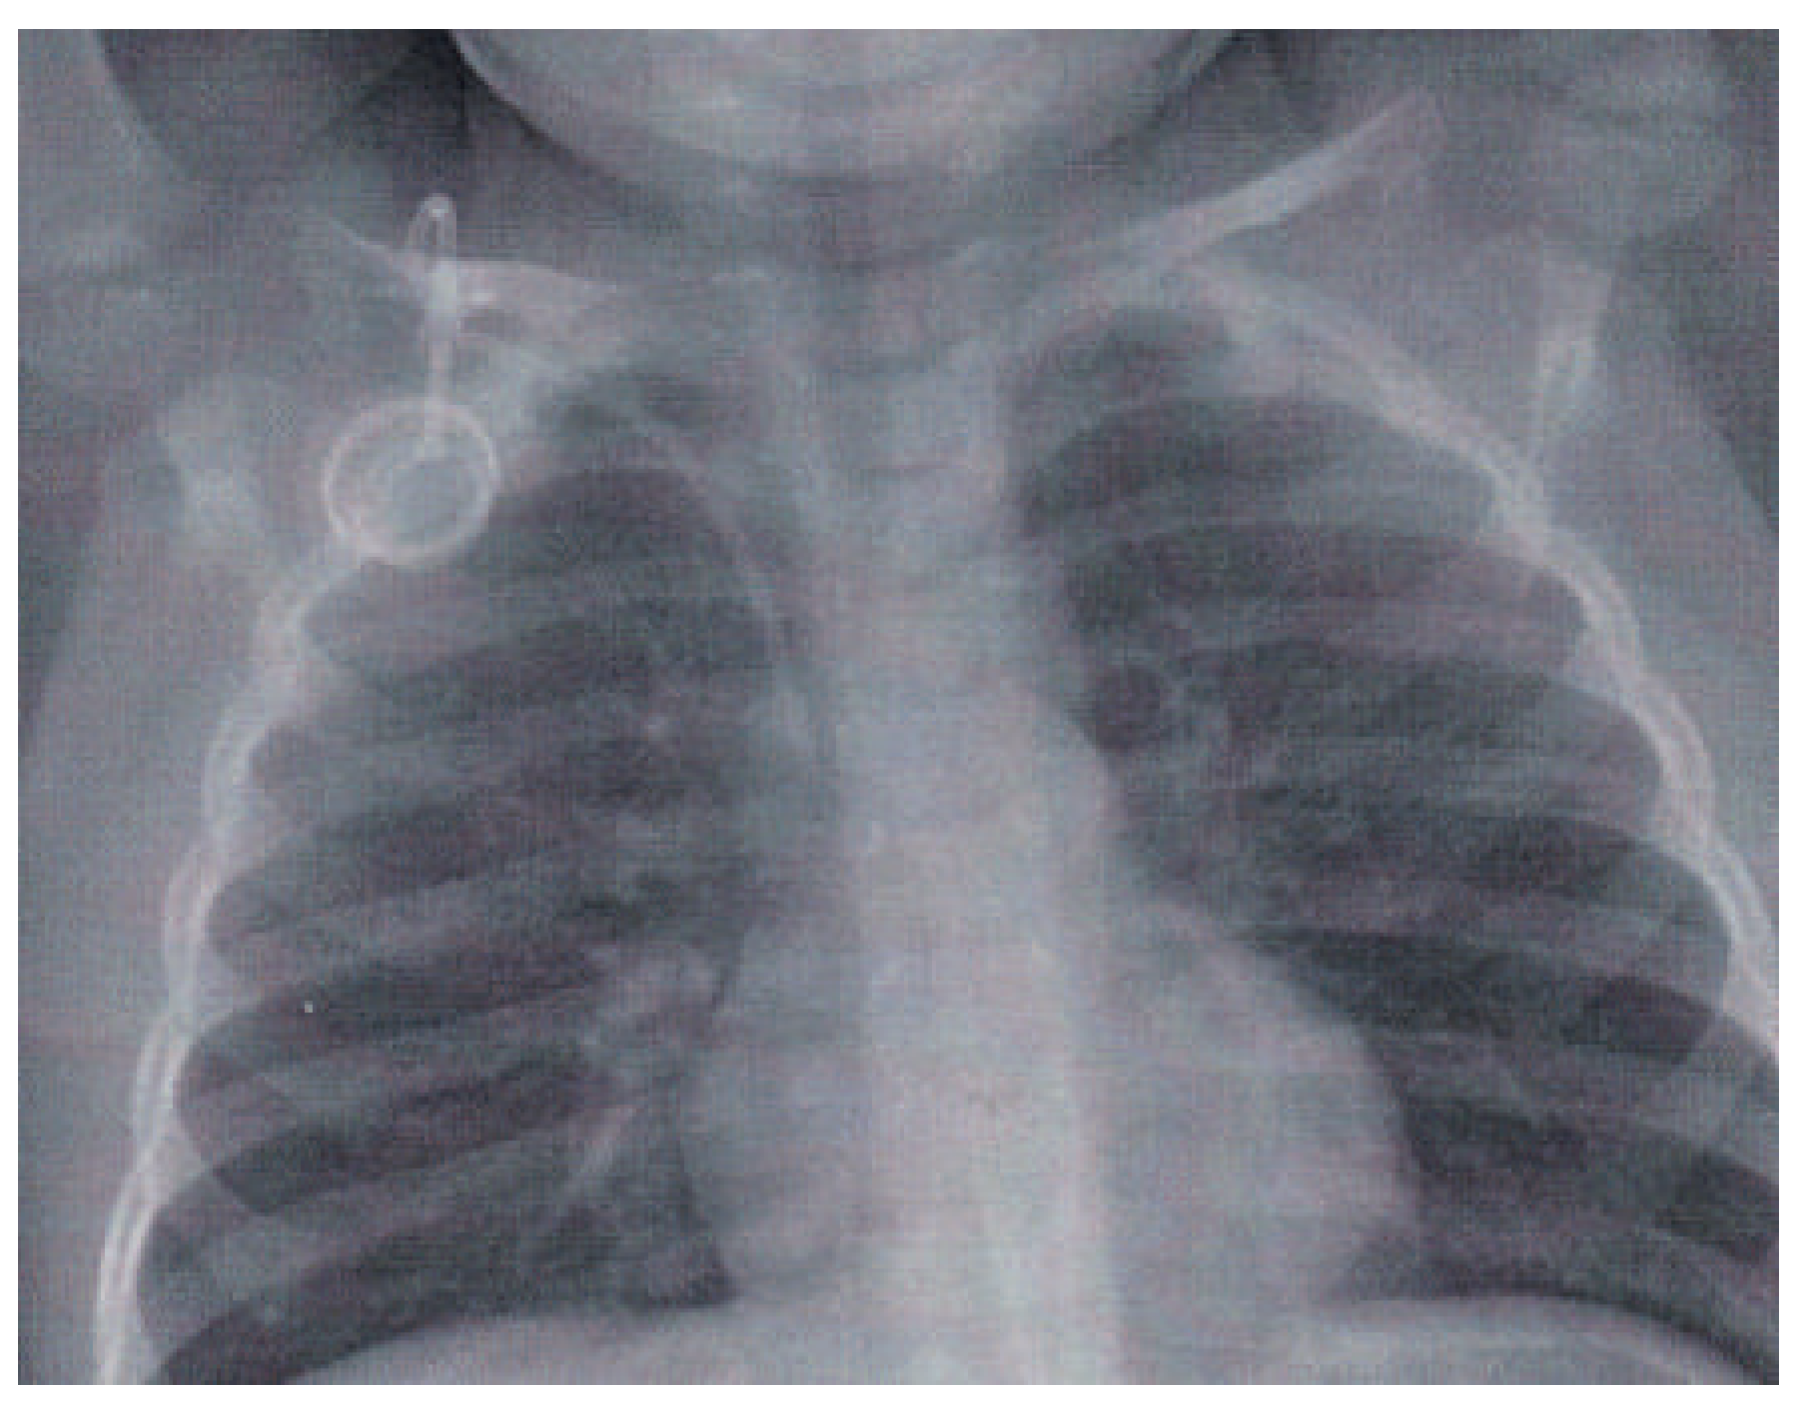

Aher the end of treatment and uneventful follow-up it was decided to remove the Port-a-Cath system surgically. A chest X-ray was performed prior to the intervention (Figure 2), which showed that, in the meantime, asymptomatic disconnection of the canula from the box of the system had occurred.

The catheter embolised into the heart, with one end of the canula being in the right atrium just above the tricuspid valve while the other end passed a patent foramen ovale (PFO) and remained stuck in the ostium of the upper leh pulmonary vein, as also verified by echocardiography.

Figure 2. Chest X-ray 3 years after implantation of the Porta-Cath prior to planned surgical removal of the system: the canula is disconnected from the box and straddles the PFO with the proximal end in the right atrium and the distal end in the upper left pulmonary vein, the catheter tip is seen just protruding outside the radiological heart shadow.